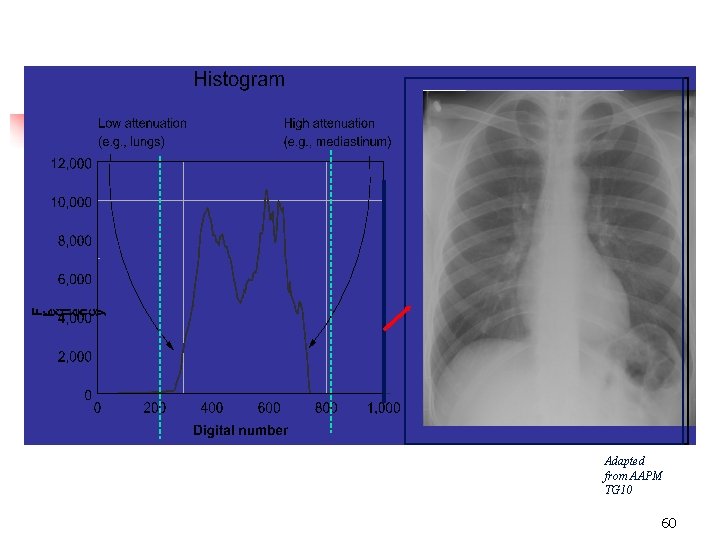

Histogram Analysis 1. 2. 3. A histogram is a plot of gray scale value vs. the frequency of occurrence (# pixels) of the gray value in the image 58

n n HISTOGRAM – a bar graph depicting the density distribution (in numerical values) of the imaging plate ALGORITHM – a set of mathematical values used to solve a problem or find an average 59

Adapted from AAPM TG 10 60

Statistical plots of the frequency of occurrence of each pixel's value 61

n The algorithm attempts to distinguish among the parts of the histogram which represent the range of densities from bone to soft tissue 65

n n n Histograms set for specific exams (body parts) Should produce digital images that are consistent (regardless of k. Vp or m. As used) Correct Algorithm (body part) must be selected prior to processing imaging plate 66